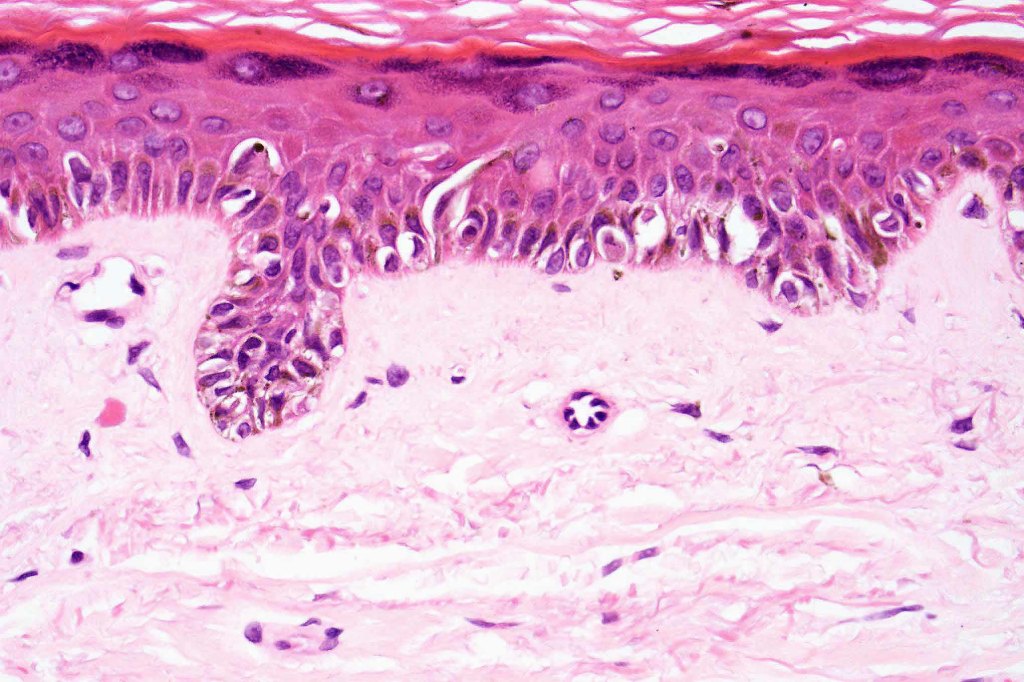

- A broad lentiginous proliferation of atypical melanocytes unasscoiated with any loss of the rete ridges

2. Melanocytes generally small, epithelioid (rather than spindled) with either vesicular nuclei and prominent nucleoli or are hyperchromatic.

3. The cells can be present singly, in short pallisades or can extend along a large section of epidermis

4. Pagetoid spread is sometimes seen in more established lesions